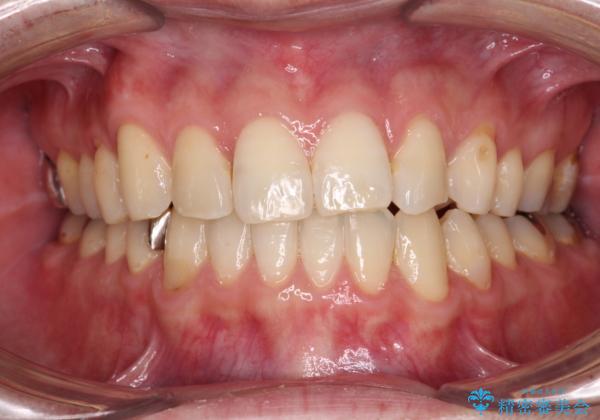

- 1年10ヶ月

インビザライン矯正は、1日22時間を目安に装着する必要がありますが、しっかりと装着してくださったので、順調に治療を進めることができました。